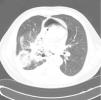

Los casos documentados de cáncer de pulmón complicados por neumomediastino o neumopericardio son extremadamente infrecuentes. Presentamos el caso de un varón de 55años de edad con cáncer de pulmón complicado por un neumomediastino y neumopericardio. El paciente fue ingresado con una clínica de disnea de 3meses de evolución (día1). Se realizó una tomografía computarizada (TC) y se estableció un estadio de la enfermedad cT4N3M0, aunque no se confirmó histopatológicamente el tumor. Se observó una invasión del pericardio y la tráquea que provocaba la formación de una fístula traqueomediastínica, un neumomediastino (fig. 1) y un neumopericardio. No se identificaron metástasis a distancia. Se llevó a cabo una broncoscopia, que mostró una estenosis tumoral importante en la tráquea aproximadamente 6cm por debajo de la glotis. El broncoscopista no pudo obtener muestras y tuvo que interrumpir la exploración prematuramente a causa de la disnea.

Se consultó al equipo de broncología invasiva, pero se llegó a la conclusión de que no era posible una intervención broncológica (no se disponía todavía de stents en Y en el centro en ese momento). El paciente presentó un deterioro rápido de su estado y falleció el día10. La autopsia reveló la presencia de un cáncer de pulmón espinocelular con invasión directa del pericardio y la tráquea formando una fístula traqueomediastínica; neumohidropericardio, neumonía del pulmón izquierdo (que no estaba presente en el momento de obtener la TC). No se identificaron metástasis a distancia, por lo que se confirmó el estadio pT4 y pM0 (no se comentó si había invasión de ganglios linfáticos N3).